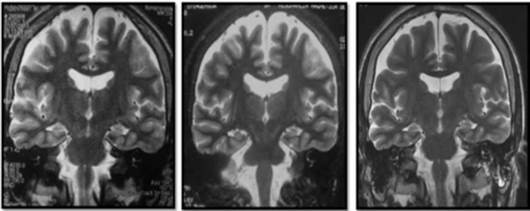

Cerebral nuclear magnetic resonance (NMR) showed generalized cortical atrophy and bilateral hippocampal atrophy (Figure 1), while electroencephalogram revealed independent bilateral temporal ictal activity, frequently associated with bradycardia and hypoxemia (Figure 2).

Simple cerebral magnetic resonance, T2 sequence. From left to right: 2008 (11 years old), 2011 (14 years old), 2016 (19 years old).

Figure 1: Simple cerebral magnetic resonance, T2 sequence. From left to right: 2008 (11 years old), 2011 (14 years old), 2016 (19 years old).

Source: Own elaboration based on the data obtained in the study.

With respect to neuroimaging, the variations observed in the MRI range between normal findings and different degrees of atrophy and hyperintensities in the temporal lobe, mainly in the hippocampal region 12,25,26, as well as in the insula and basal ganglia 11, perhaps secondary to prolonged neuronal activation 4.